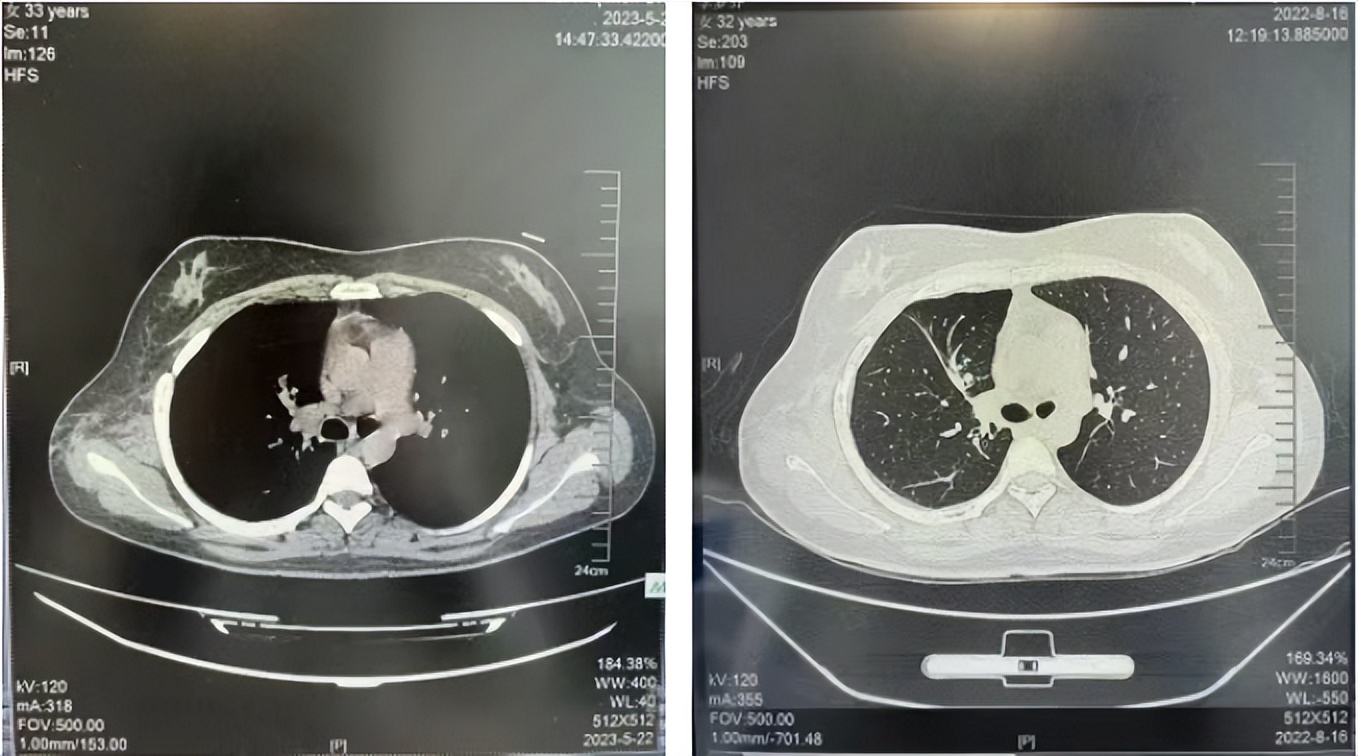

2016年1月复查CT提示支气管截断可见新发小结节,一线治疗采用培美曲塞+DDP方案化疗4周期(培美曲塞3.36,DDP 480mg)。化疗后复查胸部CT:右肺见不规则结节样影,最大层面大小约19mm*8mm,较前比较明显增大,疗效评估PD。2017.3-2017.4予单药多西他赛化疗3周期,疗效评估SD。2018年5月末复查CT提示结节较前增大,评效为PD,2018年6-10月予多西他赛+CBP化疗4周期,疗效评估SD。2022年5月患者出现活动后气短,复查胸部CT示右肺膨胀不良;右侧胸腔积液增多。胸腔积液包埋病理示符合肺腺癌细胞。行NGS基因检测:EML4:exon13-ALK:exon20融合。PD-L1(克隆号22C3)TPS<1%。

临床诊断:右肺上叶恶性肿瘤rT0N0M1a IVA期(第9版分期);恶性胸腔积液。

诊疗经过:2022年5月始口服克唑替尼3个月,出现肝功能异常(DILI 2级伴临床症状),改用恩沙替尼靶向治疗至今,目前评效为维持PR。恩沙替尼应用期间出现轻度肝功能异常(DILI 1级),对症处理后好转。截止目前PFS 33个月。

2018.07

2022.05

2022.08

2023.05